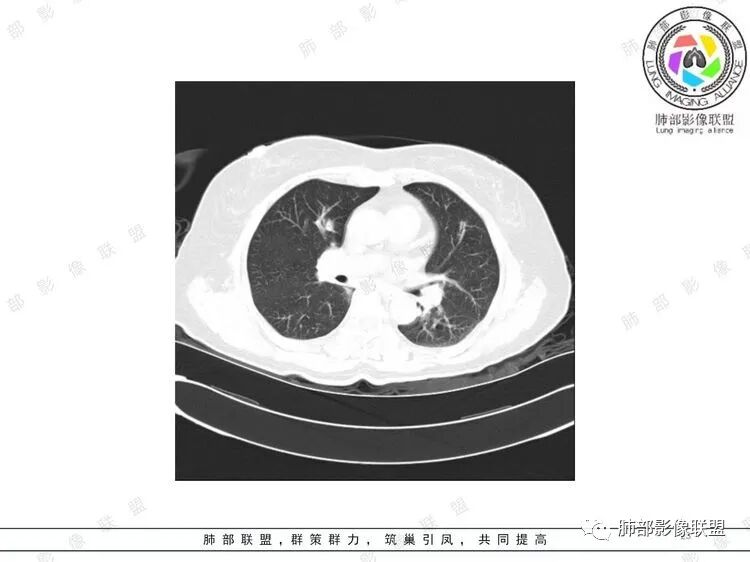

胸CT:双中下肺支气管壁明显增厚,双下肺胸膜下可见实变区。部分病变呈楔形影。

老年女性,咳嗽咳痰低热20天,双肺野散在结节影,随机分布,双肺下叶支气管血管束增粗,支气管管腔狭窄,胸膜下结节斑片影,临床有血尿,痰培养白念阳性,低氧血症。血管炎抗体阴性。从影像看主要侵犯的是血管,血管壁增厚,血管炎抗体阴性不大支持,患者有血尿,考虑膀胱肿瘤引起转移,但是膀胱彩超没发现占位,估计血尿是膀胱炎引起。从影像看考虑侵袭性曲霉菌病?血管炎?实在没有思路。

双肺多发大小不等结节,周围伴有晕征,边界模糊,部分结节内似可见支气管影,双肺血管束明显比支气管增粗,临床有感染症状,考虑GPA,疱疹病毒。

双肺支气管管壁弥漫性增厚,管腔狭窄,下叶为主,伴多发高密度结节影,边缘模糊,双肺支气管血管束明显增粗,临床症状咳嗽低热,有血尿,首先考虑血管炎

影像上:多发结节沿血管分布;双下叶支气管血管束简直增厚,偏血管,支气管通畅

因为支气管壁增厚,远端应该小气道病变,这个不是,反而是血管增粗明显

加上结节的分布,支持血管相关病变